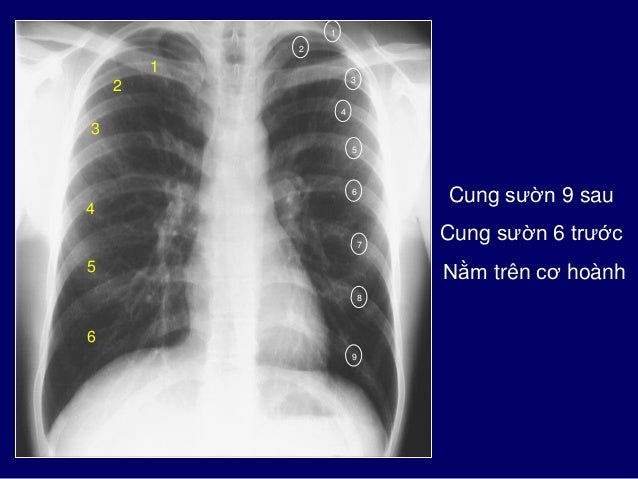

6. 6. Hít không đủ sâu  Mờ vùng đáy giả tạo Hít lại cho đủ sâu  Biến mất vùng mờ ở đáy

7. 7. Cung sườn 9 sau Cung sườn 6 trước Nằm trên cơ hoành 1 2 3 4 5 6 7 8 9 1 2 3 4 5 6